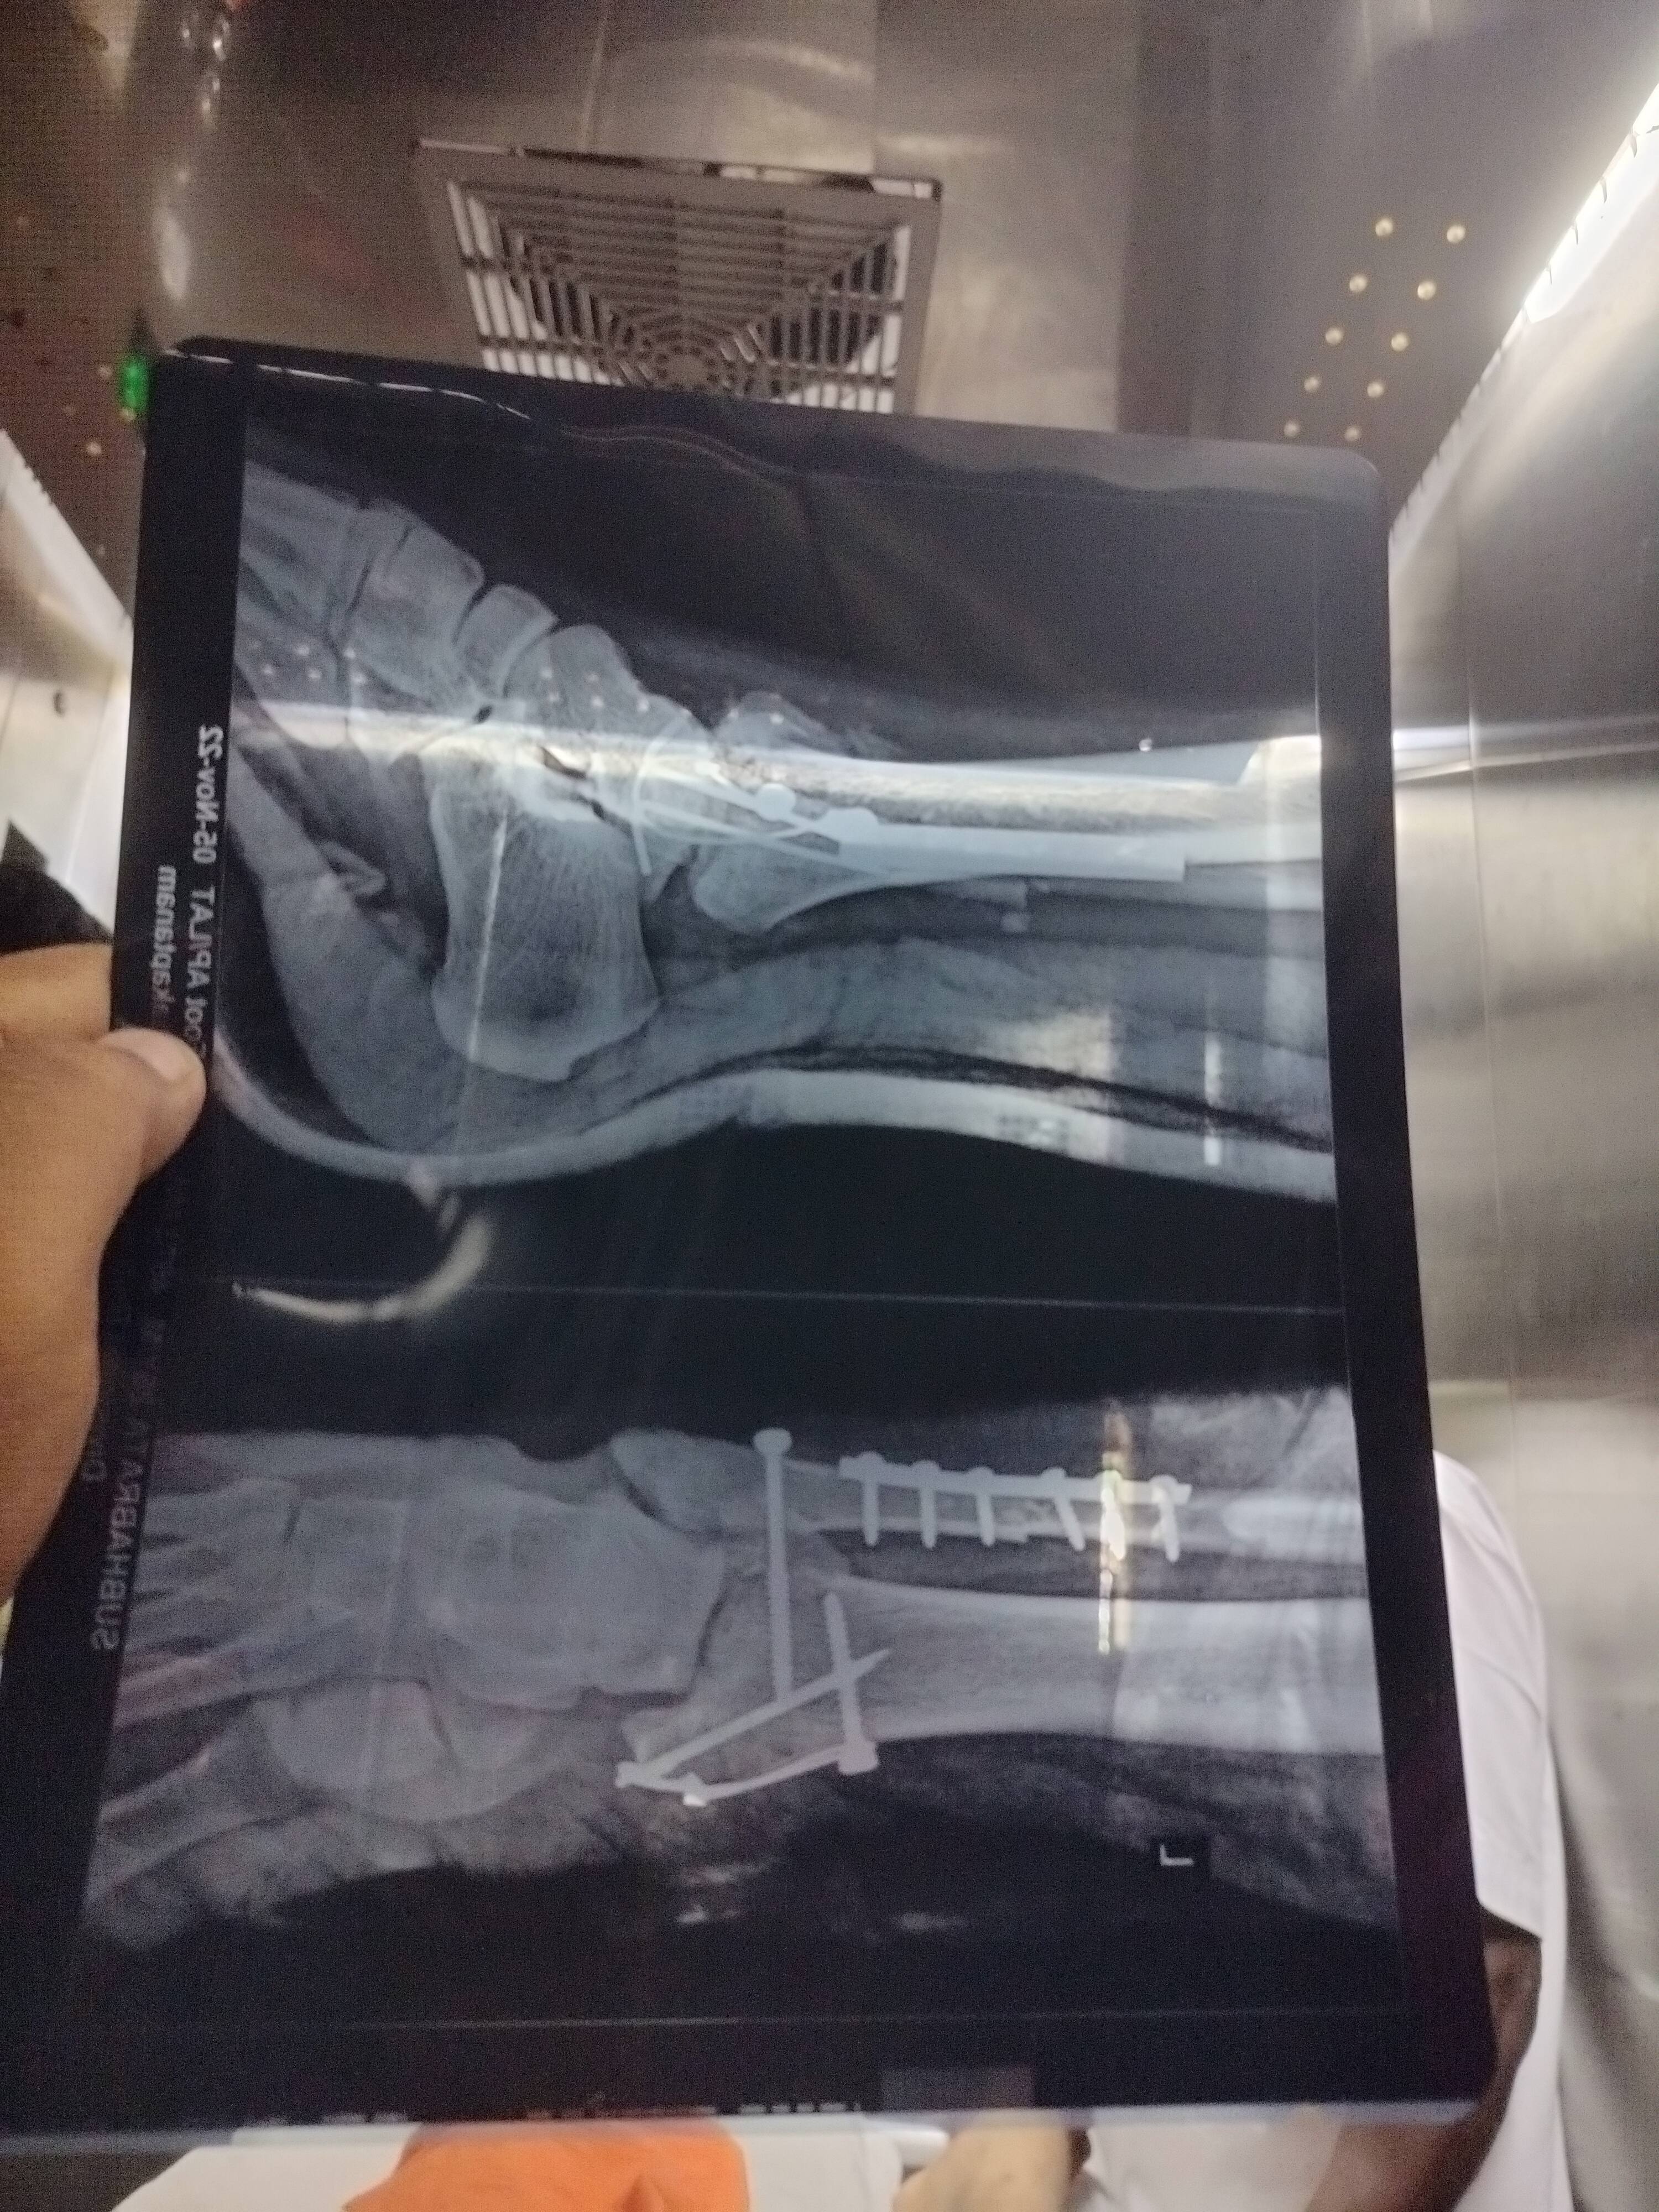

you will improve with time and physiotherapy